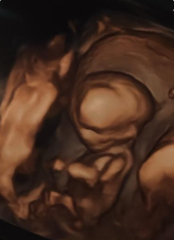

Thanks everyone - didn't get a call back from EPU yesterday so went for a private scan in the evening and luckily everything is ok! Baby is still very active and measuring a couple of days ahead of where expected

Had a sneak 3d preview too which is really weird!!! My boyfriends first comment was that it looks like Voldemort 😂😂😂

@DramaticFridge What an adorable ultrasound! The 3d ones always scare me a bit :D I'm so glad everythings alright with you!

@DramaticFridge Wonderful pics and glad all is ok!

@DramaticFridge Glad everything is ok, lovely scan pics!